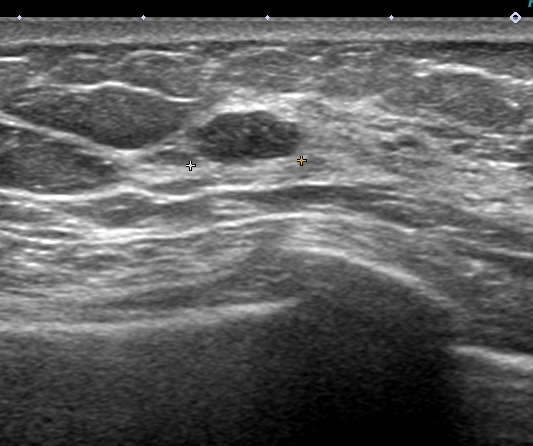

これも検診時の画像

左はエラストグラフィー(硬さを見ています 赤:柔らかい 青:硬い)

皮下脂肪は赤で柔らかく

腫瘍(中心:青)は周囲の乳腺(緑)よりも硬いことがわかります。